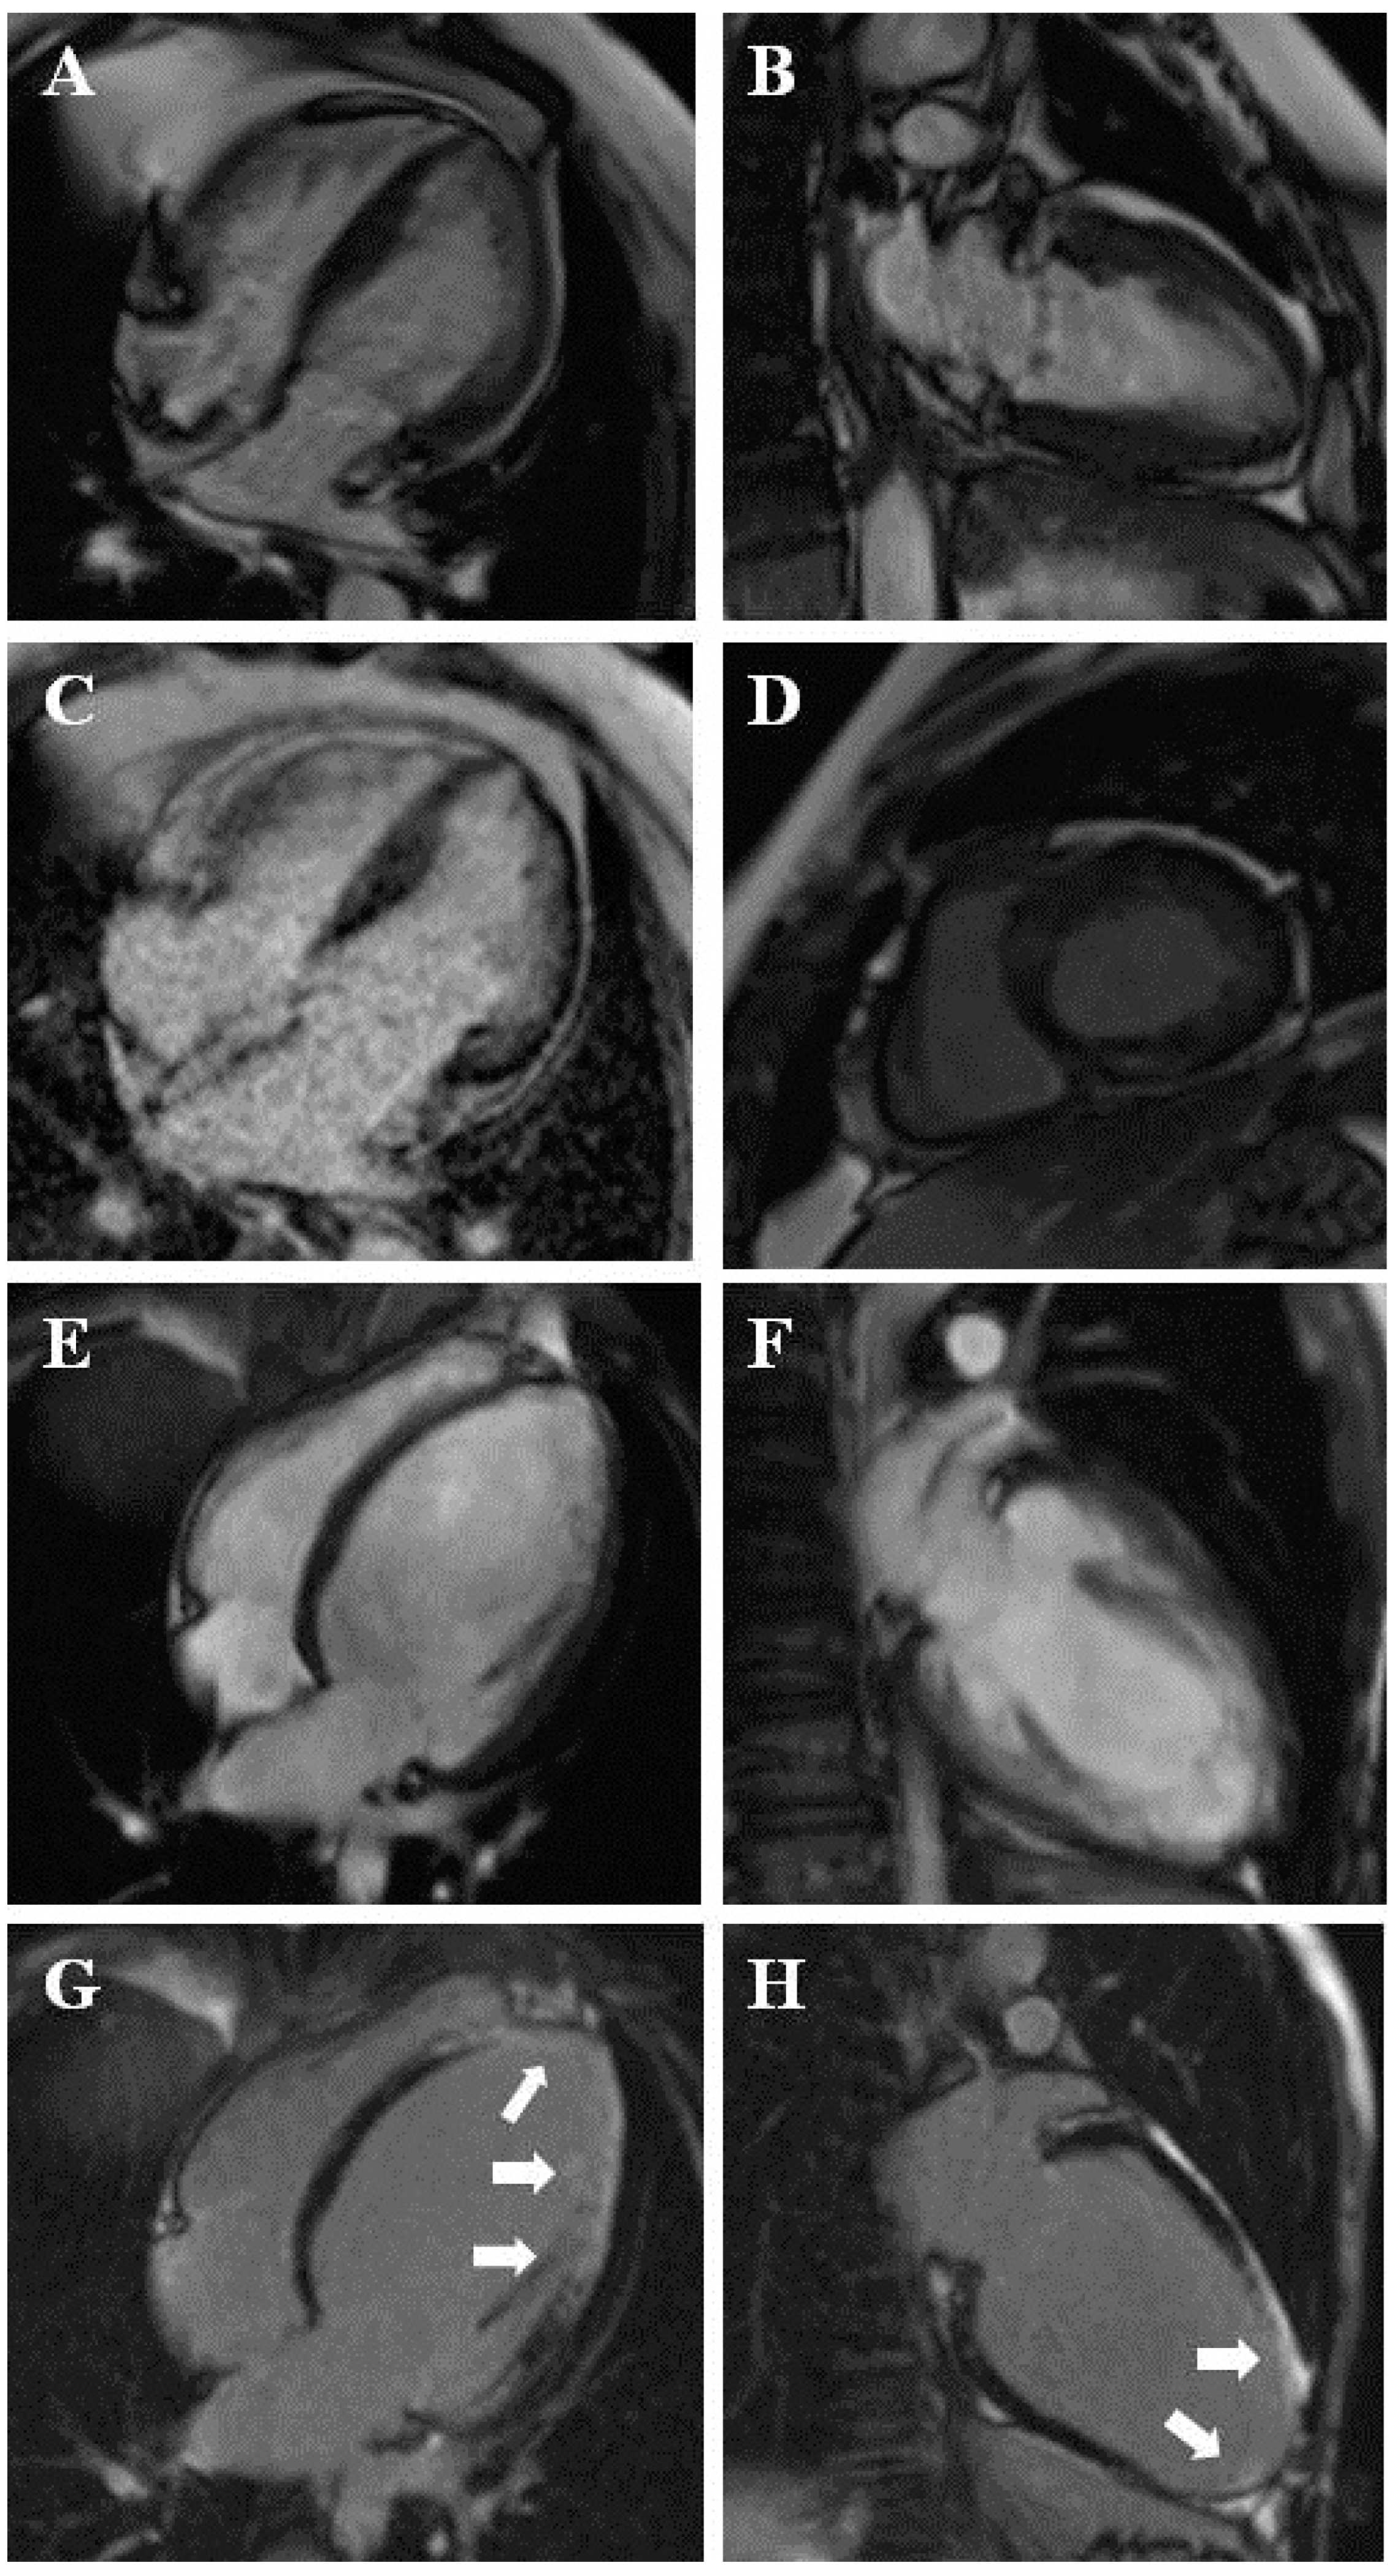

Impact of Cardiac Magnetic Resonance on the Diagnosis of Left Ventricular Noncompaction—A 15-Year Experience

3.2. CMR Diagnosis